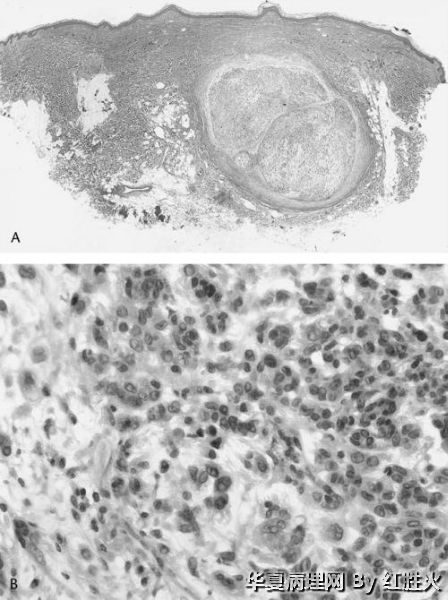

文献中描述的神经母细胞瘤样神经鞘瘤的组织学特点是具有巨大的菊形团结构,细胞呈淋巴细胞样,细胞浆稀少;部分病例也有上皮样特点区域。因此从形态描述上,神经母细胞样神经鞘瘤与上皮样神经鞘瘤有共同点,有时难以区分。但是从实际诊断的角度,应当抓住病变的主要特征,当以菊形团结构为主时,宜诊断神经母细胞瘤样神经鞘瘤,当以上皮样细胞为主时,宜诊断上皮样神经鞘瘤。本例以上皮样特点为主,所以宜诊断为上皮样神经鞘瘤。

这是一个很有意义的病例,引起众多网友的关注和热烈讨论并发表了很好的意见。本例为青年男性,下肢肿物数年,最大径只有1.5㎝,且为以囊性为主的囊实性肿瘤,镜下改变缺少明显异型性、核分裂和坏死,有包膜,均提示可能为良性肿瘤。讨论意见集中于神经鞘瘤说明大家都有相当高的水平。

本例具有部分经典神经鞘瘤的形态特点,如有细胞密集区和疏松黏液样区、血管壁透明变性;又有其特殊形态,既可见菊形团样结构。因而争论的焦点在于是上皮样神经鞘瘤不是神经母细胞瘤样神经鞘瘤,这两种神经鞘瘤的亚型分别于1998和1994年见于文献报道,本例虽有菊形团样结构,但菊形团较小不够突出,另外其瘤细胞胞质较为丰富呈上皮样(神经纤维瘤样神经鞘瘤的瘤细胞缺少胞质),HE形态诊断上皮样神经鞘瘤更为客观,加做Ⅳ型胶原如能显示瘤细胞周围的基底膜样物质,则可进一步证实。

诊断:上皮样神经鞘瘤。